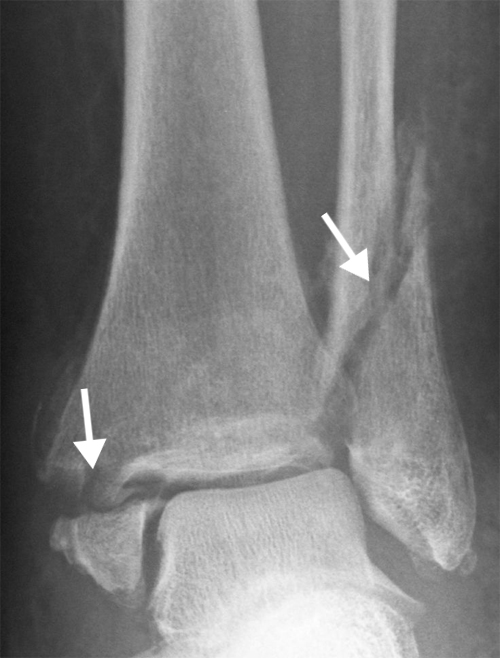

The diagnosis is confirmed through the physical examination and an X-ray.